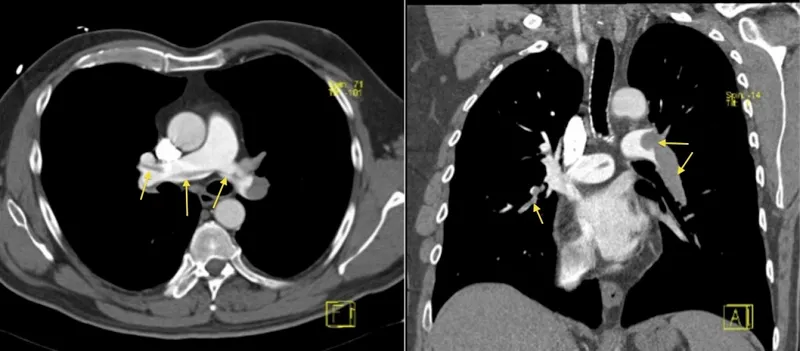

- CT Pulmonary Angiography (CTPA): Gold standard.